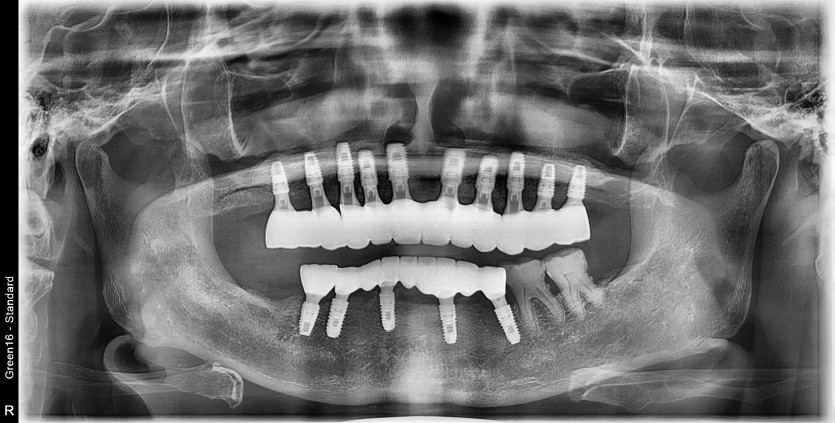

상악 전체 임플란트 증례입니다.(하악 일부)

11개의 임플란트로 완성하였습니다.